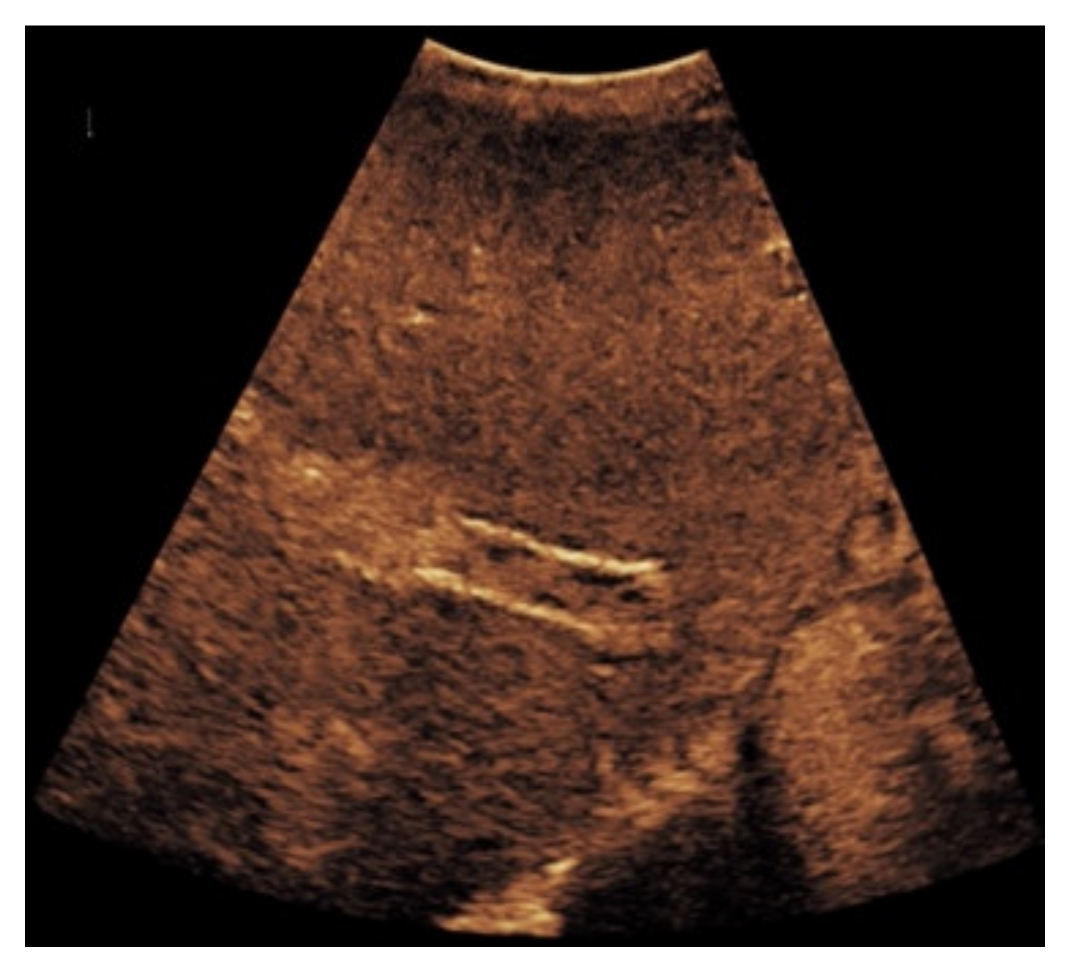

Figure 4. Same patient as in Figure 1 with continuous flow within the transjugular intrahepatic portosystemic shunt (TIPS) without thrombosis or occlusion using microflow imaging (a) and after administration of contrast agent (b,c).

Based on initial findings from CDUS, 67% (n = 71) of the patients showed normal perfusion within the TIPS (Figure 1). 18% (n = 19) of the cases presented stent occlusion (Figure 2) while 6% of the patients (n = 6) had partial occluding stent thrombosis (Figure 3). The TIPS perfusion in five patients was only partially assessable, while in two patients an examination was not feasible due to extensive meteorism. The patients listed under “others” showed postoperative entrapped air between the wall of the vessel and the stent (n = 2) while one patient had two TIPS, one occluded and one with a normally detectable blood flow (Table 1).

When taking a closer look at the results of the CEUS examinations, 70.8% (n = 75) of the patients showed regular stent perfusion (Figure 4), 17.9% (n = 19) of the patients featured TIPS occlusion (Figure 5) while 6.6% (n = 7) patients had stent thrombosis (Figure 6). In contrast to the results from CDUS, there were no patients with only partial accessibility of the TIPS during CEUS, while the two patients with meteorism also were not assessable during CEUS. The three patients categorized in “others” showed simultaneous findings between CDUS and CEUS (Table 2).